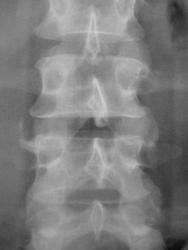

Иллюстрации 1, 2. На обзорной рентгенограмме области почек и мочевыводящих путей слева на уровне Т12 и Л1 определяются две тени характера конкрементов различных размеров значительной интенсивности неоднородной структуры.

Иллюстрация 3. Определяется ротация тела Л3. На уровне сегмента Л3 – Л4 определяется локальное окостенение передней продольной связки, по всей видимости, в результате подсвязочного костеообразования. Определяется некоторая ротация тела Л3.